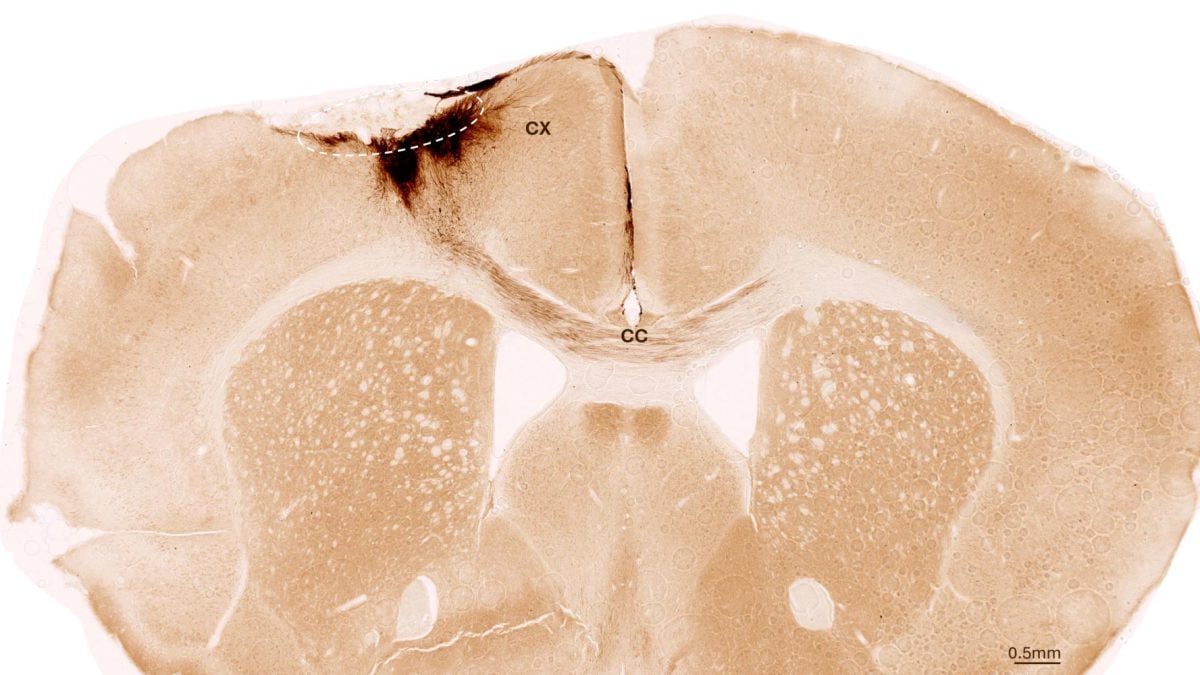

Hình ảnh này chụp cắt lớp não chuột sau đột quỵ và ghép tế bào gốc thần kinh, với vòng tròn nét đứt đánh dấu vùng bị đột quỵ, trong khi các nhánh thần kinh được tạo ra từ tế bào gốc của người được tô màu nâu sẫm - Ảnh: ĐẠI HỌC ZURICH

Nhóm nghiên cứu đã thí nghiệm những con chuột bị đột quỵ và được biến đổi gene để không đào thải tế bào của con người.

Một tuần sau cơn đột quỵ, những con vật này được ghép tế bào gốc thần kinh của người, là loại tế bào có thể biến đổi thành các loại tế bào khác nhau của hệ thần kinh.

"Chúng tôi phát hiện ra rằng các tế bào gốc sống sót trong suốt thời gian phân tích kéo dài 5 tuần và hầu hết chúng đã chuyển hóa thành tế bào thần kinh, thậm chí còn giao tiếp với các tế bào não đã tồn tại" - đồng tác giả Christian Tackenberg từ Đại học Zurich nói với SciTech Daily.